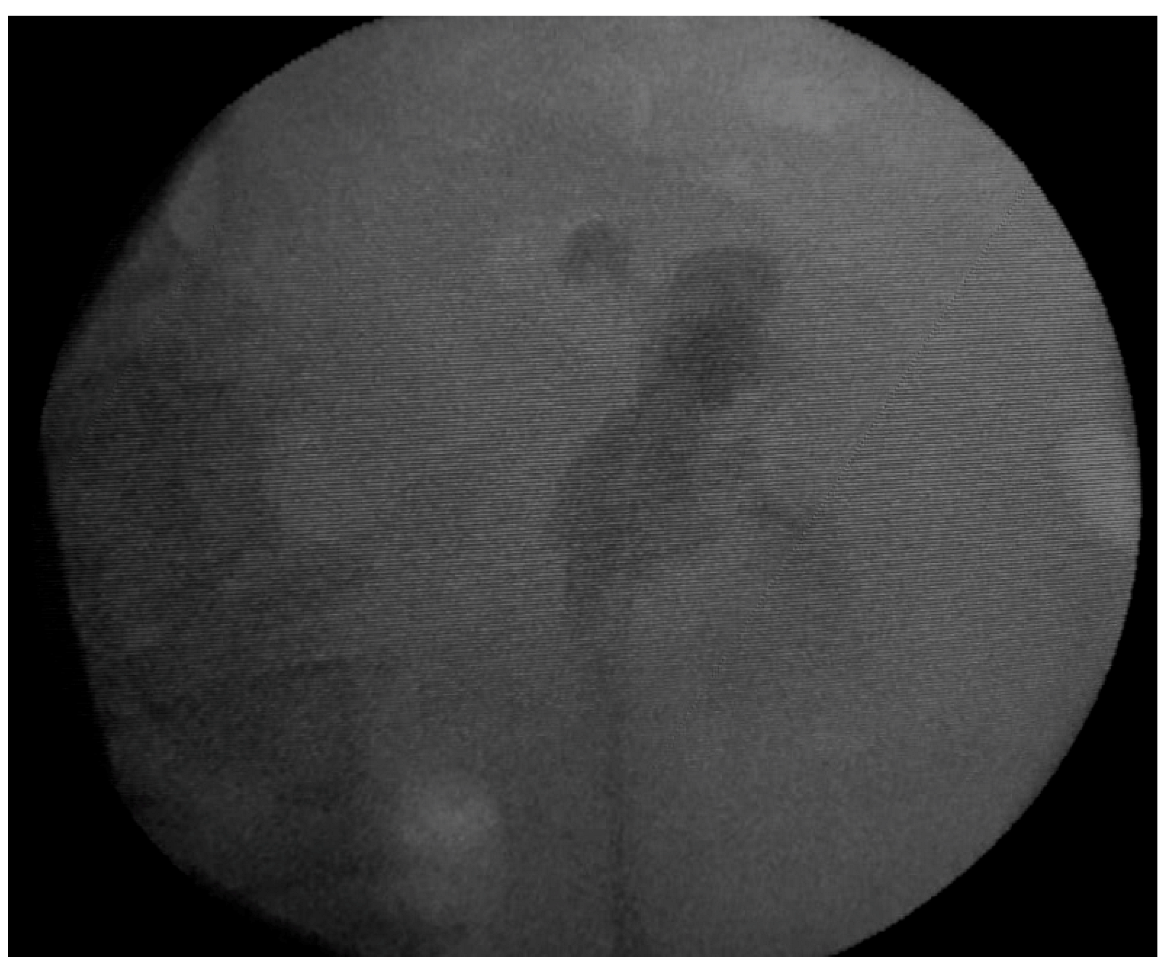

Emergency abdominal and pelvic non-contrast CT scan showed multiple thin left ureteral, pyelic, and calyceal calcifications on the surface of the urothelium, which are specific to encrusted uretero-pyelitis, with a maximum density of 510 Hounsfield units and with a mild dilation of the upper left urinary tract, right kidney hypoplasia, and enlarged retroperitoneal lymph nodes (Figure 1 and Figure 2).

Figure 1. Axial plane images of abdominal and pelvic CT scan without contrast showing multiple pyelic, calyceal, and ureteral calcifications specific to encrusted uretero-pyelitis.